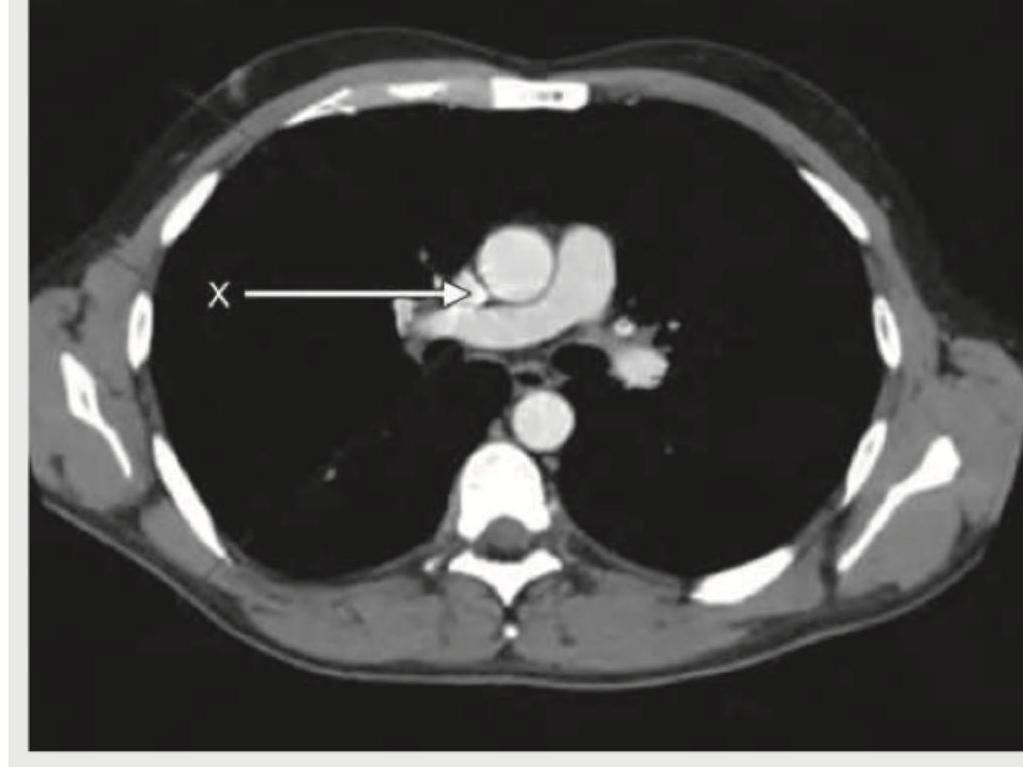

The X mark in the following CT chest shows:

Explanation: ***Ascending aorta*** - The arrow points to a circular, bright white structure in the anterior mediastinum, which is the **ascending aorta** enhanced with contrast. - Its position anterior to the trachea and superior to the main pulmonary artery is characteristic of the ascending aorta at this CT level. *Descending aorta* - The **descending aorta** is positioned more posteriorly and to the left of the vertebral body at this level; the structure indicated is clearly in the anterior mediastinum. - It would appear as a separate, contrast-enhanced circular structure behind the heart and often slightly to the left of midline. *Superior vena cava* - While also in the anterior mediastinum, the **superior vena cava (SVC)** is typically a thinner-walled, more ovoid structure and lies to the right of the ascending aorta. - The indicated structure is distinctly thick-walled and circular, typical of an artery, not a vein. *Inferior vena cava* - The **inferior vena cava (IVC)** is located much lower in the chest and abdomen, and it is not visible at this axial CT level through the great vessels. - At the level of the great vessels, the IVC would be out of the displayed field or would appear more inferiorly, entering the right atrium.